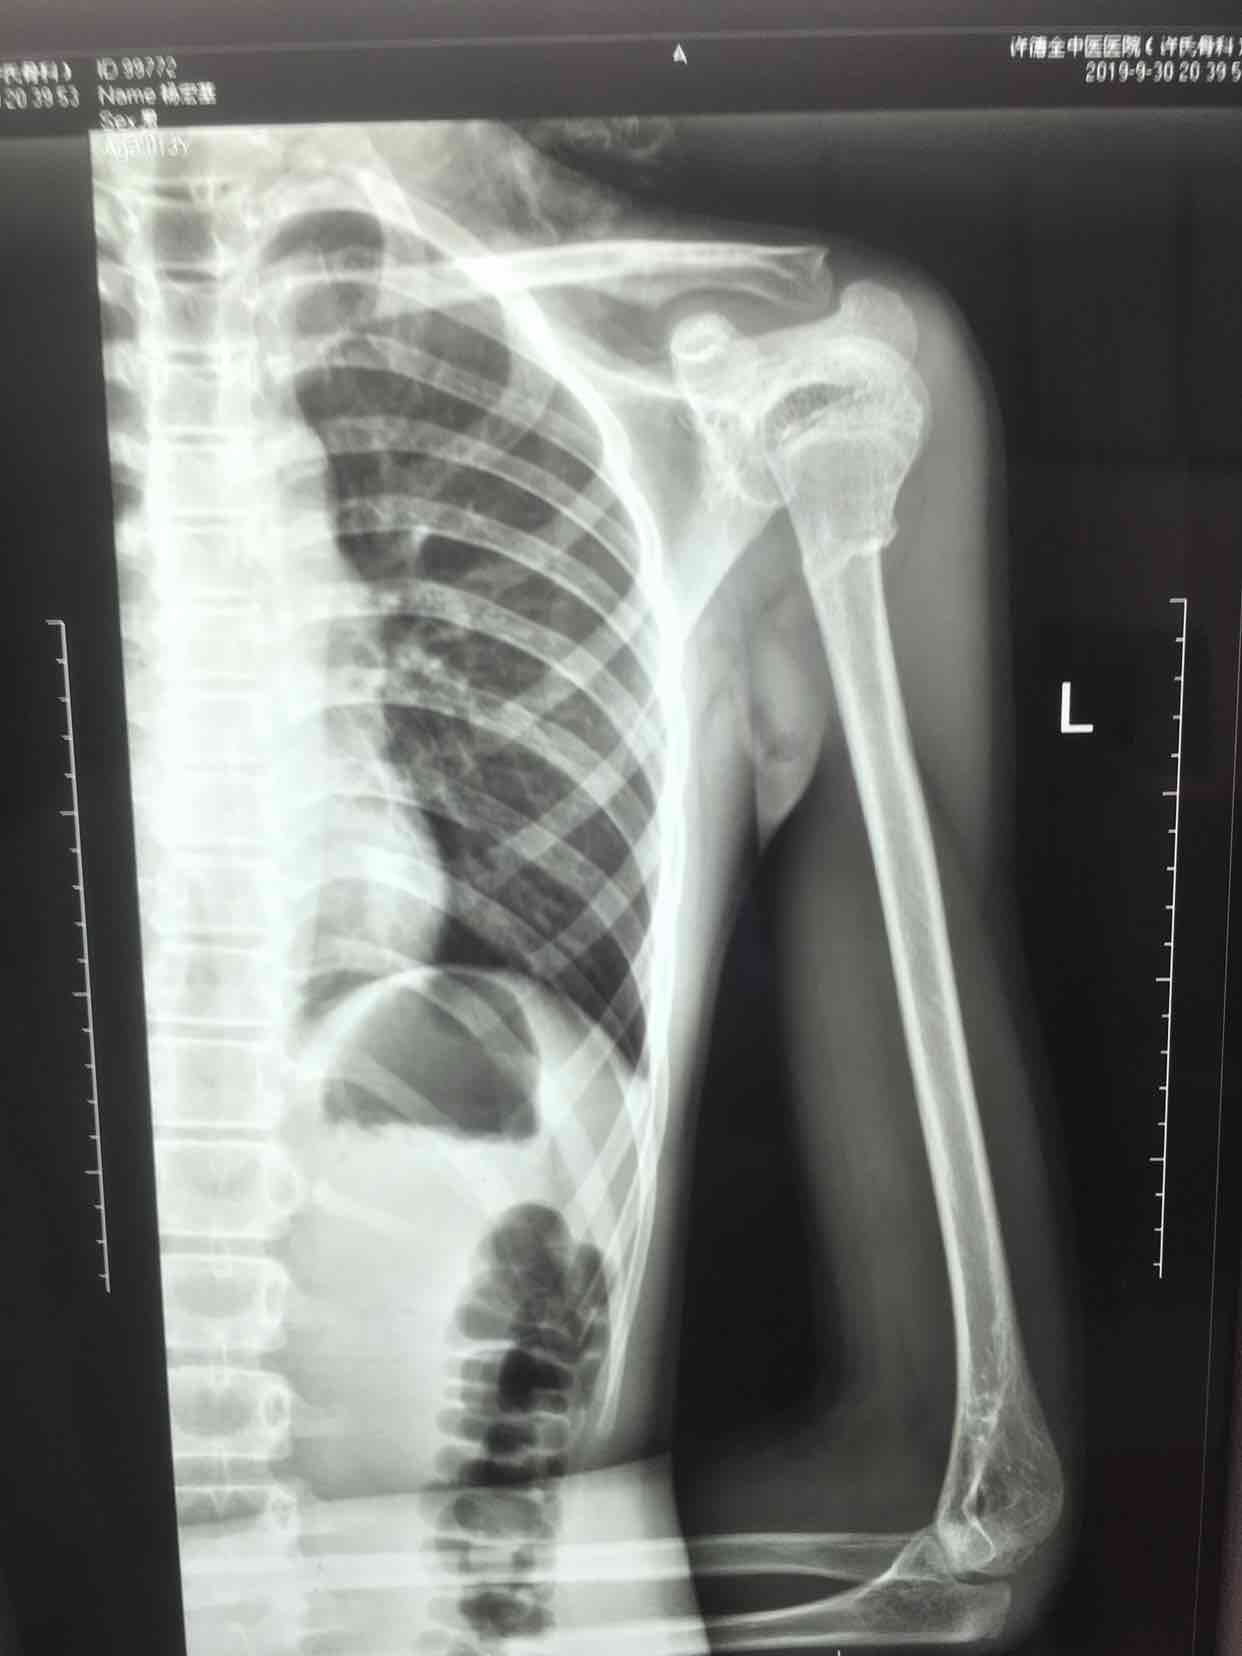

骨折 肱骨外科颈骨折

摔伤后左肩部肿痛,活动受限1小时入院。既往身体健康,无特殊不良嗜好。

生命体征平稳,心肺复未见异常。左肩部肿胀明显,局部皮色皮温正常,压痛及纵向叩击痛阳性,肩关节活动受限,末梢血运感觉正常。